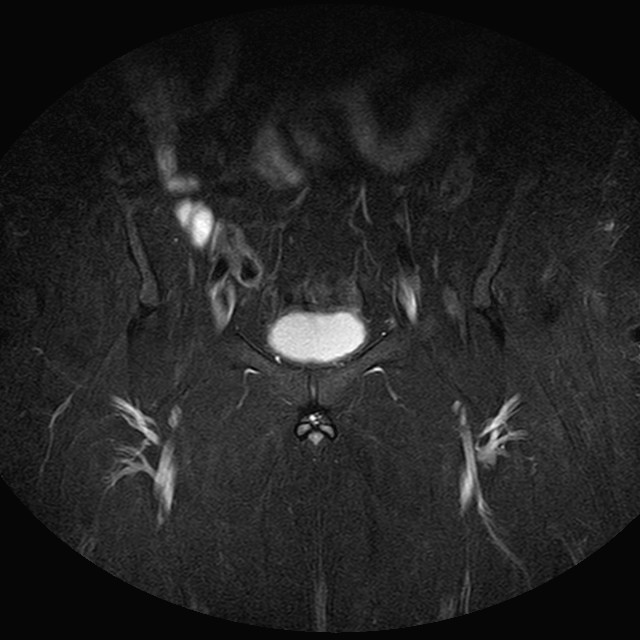

eSTIR

Evidenti e simmetriche alterazioni osteofitosiche in regione coxo femorale con riduzione delle rime articolari. Degenerazione completa del cercine glenoideo. Non attuali segni di versamento articolare. Non segni di edema osseo che escludono attuale algodistrofia od osteonecrosi. Lieve e simmetrica riduzione del trofismo della muscolatura glutea.